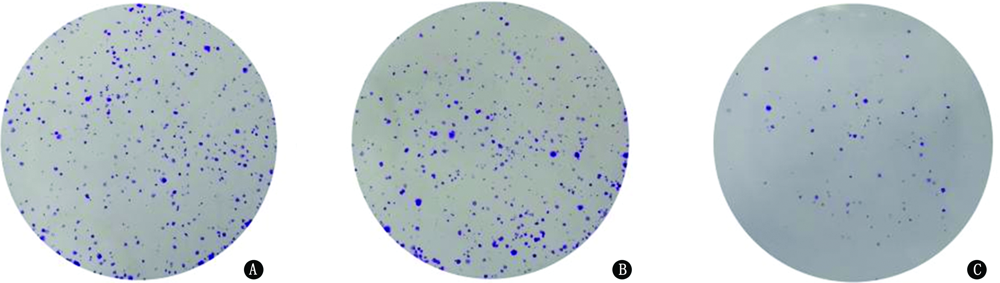

目的 探讨活化T细胞核因子5(NFAT5)在肺腺癌组织及细胞中的表达以及抑制NFAT5对肺腺癌细胞增殖、侵袭、迁移及凋亡能力的影响。方法 收集2017年6月至2019年6月在解放军联勤保障部队第九〇四医院接受诊断和治疗的61例肺腺癌患者的临床病理标本和癌旁组织,采用实时荧光定量PCR(qRT-PCR)检测肺腺癌组织、癌旁组织中NFAT5的表达水平,并分析NFAT5的表达水平与患者临床病理特征的关系。将H1975细胞分为对照组(不作任何处理)、NC组(转染siRNA-NC)和si-NFAT5组(转染siRNA-NFAT5),采用qRT-PCR检测细胞株中NFAT5的表达水平,采用MTT和克隆形成实验检测细胞增殖情况,Transwell和划痕实验检测细胞侵袭和迁移能力,流式细胞仪检测细胞凋亡情况,蛋白质印迹法检测细胞丝裂原活化蛋白激酶(MAPK)信号通路相关蛋白的表达。结果 NFAT5 mRNA在肺腺癌组织中的表达量(3.22±0.20)显著高于癌旁组织(1.00±0.12),差异具有统计学意义(t=75.662,P<0.001);肺腺癌组织中NFAT5的表达水平与肿瘤TNM分期(χ2=10.357,P=0.001)和淋巴结转移(χ2=18.268,P<0.001)有关。NFAT5在对照组、NC组、si-NFAT5组中的相对表达量分别为1.00±0.06、1.01±0.05、0.31±0.06,差异具有统计学意义(F=140.498,P<0.001)。对照组、NC组和si-NFAT5组3组H1975细胞转染24 h后吸光度(A)值分别为0.70±0.01、0.55±0.01、0.35±0.01,48 h后分别为0.92±0.03、0.87±0.06、0.57±0.06,72 h后分别为1.05±0.01、0.90±0.01、0.66±0.01,差异均具有统计学意义(F=9.815,P=0.013;F=45.977,P<0.001;F=129.494,P<0.001),进一步两两比较,24、48、72 h si-NFAT5组增殖能力均明显低于对照组和NC组(均P<0.001)。3组细胞克隆数分别为452.33±31.50、421.00±17.35、129.00±17.35,差异具有统计学意义(F=128.200,P<0.001);si-NFAT5组细胞克隆数较对照组和NC组均显著下降(均P<0.001)。3组细胞侵袭数目分别为262.67±28.02、278.00±27.50、46.00±12.00,差异具有统计学意义(F=89.896,P<0.001);si-NFAT5组细胞侵袭能力较对照组和NC组均显著降低(均P<0.001)。3组细胞相对划痕宽度分别为0.28±0.04、0.32±0.04、0.54±0.04,差异具有统计学意义(F=42.889,P<0.001);si-NFAT5组细胞相对划痕宽度较对照组和NC组均显著增加(均P<0.001)。3组细胞凋亡率分别为(3.38±0.56)%、(3.14±0.62)%、(13.82±0.75)%,差异具有统计学意义(F=264.705,P<0.001);si-NFAT5组细胞凋亡率均显著高于对照组和NC组(均P<0.001)。3组H1975细胞NFAT5、p-P38/P38、p-ERK1/2/ERK1/2、p-JNK/JNK蛋白表达差异均具有统计学意义(F=91.245,P<0.001;F=132.896,P<0.001;F=243.332,P<0.001;F=118.358,P<0.001);si-NFAT5组NFAT5、p-P38/P38、p-ERK1/2/ERK1/2、p-JNK/JNK蛋白表达较对照组和NC组均显著降低(均P<0.001)。结论 NFAT5在肺腺癌组织及细胞中的表达均升高。抑制NFAT5能够抑制肺腺癌H1975细胞增殖、侵袭和迁移,并促进H1975细胞凋亡,其机制可能与NFAT5抑制MAPK信号通路有关。

Objective To investigate the expressions of nuclear factor of activated T cell 5 (NFAT5) in lung adenocarcinoma tissues and cells, and the effects of NFAT5 on the proliferation, invasion, migration and apoptosis of lung adenocarcinoma cells. Methods The clinical pathological specimens and paracancerous tissues of 61 patients with lung adenocarcinoma diagnosed and treated in 904th Hospital of Joint Logistic Support Force of People's Liberation Army from June 2017 to June 2019 were collected. The expression levels of NFAT5 in lung adenocarcinoma tissues and paracancerous tissues were detected by quantitative real-time PCR (qRT-PCR), and the relationships between the expression of NFAT5 and clinicopathological features of patients were analyzed. H1975 cells were divided into control group (no treatment), NC group (transfecting siRNA-NC) and si-NFAT5 group (transfecting siRNA-NFAT5) . qRT-PCR was used to detect the expression level of NFAT5 in cell line. MTT and clone formation assay were used to detect cell proliferation. Transwell and scratch test were used to detect cell invasion and migration ability. Flow cytometry was used to detect cell apoptosis. The expressions of mitogen-activated protein kinase (MAPK) signaling pathway related proteins were detected by Western blotting. Results The expression level of NFAT5 mRNA in lung adenocarcinoma (3.22±0.20) was significantly higher than that in paracancerous tissues (1.00±0.12), and there was a statistically significant difference (t=75.662, P<0.001). The expression level of NFAT5 in lung adenocarcinoma tissue was associated with TNM stage (χ2=10.357, P=0.001) and lymph node metastasis (χ2=18.268, P<0.001). The expression levels of NFAT5 in the control group, NC group and si-NFAT5 group were 1.00±0.06, 1.01±0.05 and 0.31±0.06, and there was a statistically significant difference (F=140.498, P<0.001). The absorbance (A) values in the control group, NC group and si-NFAT5 group were 0.70±0.01, 0.55±0.01 and 0.35±0.01 at 24 h after transfection, 0.92±0.03, 0.87±0.06 and 0.57±0.06 at 48 h after transfection, 1.05±0.01, 0.90±0.01 and 0.66±0.01 at 72 h after transfection, and there were statistically significant differences (F=9.815, P=0.013; F=45.977, P<0.001; F=129.494, P<0.001). Further pairwise comparison showed that the proliferation abilities of the si-NFAT5 group at 24, 48 and 72 h were significantly lower than those of the control group and NC group (all P<0.001). The cell clone numbers in the three groups were 452.33±31.50, 421.00±17.35 and 129.00±17.35 respectively, with a statistically significant difference (F=128.200, P<0.001). The cell clone number in the si-NFAT5 group was significantly lower than that in the control group and NC group (both P<0.001). The invasion numbers of cells in the three groups were 262.67±28.02, 278.00±27.50 and 46.00±12.00 respectively, and there was a statistically significant difference (F=89.896, P<0.001). The cell invasive ability in the si-NFAT5 group was significantly lower than that in the control group and NC group (both P<0.001). The relative scratch widths in the three groups were 0.28±0.04, 0.32±0.04 and 0.54±0.04 respectively, and there was a statistically significant difference (F=42.889, P<0.001). The relative scratch width in the si-NFAT5 group was significantly increased than that in the control group and NC group (both P<0.001). The apoptosis rates in the three groups were (3.38±0.56)%, (3.14±0.62)% and (13.82±0.75)% respectively, and there was a statistically significant difference (F=264.705, P<0.001). The apoptosis rate in the si-NFAT5 group was significantly higher than that in the control group and NC group (both P<0.001). The differences of protein expressions of NFAT5, p-P38/P38, p-ERK1/2/ERK1/2, p-JNK/JNK among the three groups were statistically significant (F=91.245, P<0.001; F=132.896, P<0.001; F=243.332, P<0.001; F=118.358, P<0.001). The protein expressions of NFAT5, p-P38/P38, p-ERK1/2/ERK1/2, p-JNK/JNK in the si-NFAT5 group were all significantly lower than those in the control group and NC group, and there were statistically significant differences (all P<0.001). Conclusion The expression of NFAT5 is increased in lung adenocarcinoma tissues and cells. Inhibition of NFAT5 can inhibit proliferation, invasion and migration of lung adenocarcinoma H1975 cells, and promote apoptosis of H1975 cells. The mechanism may be related to the inhibition of MAPK signal pathway by NFAT5.